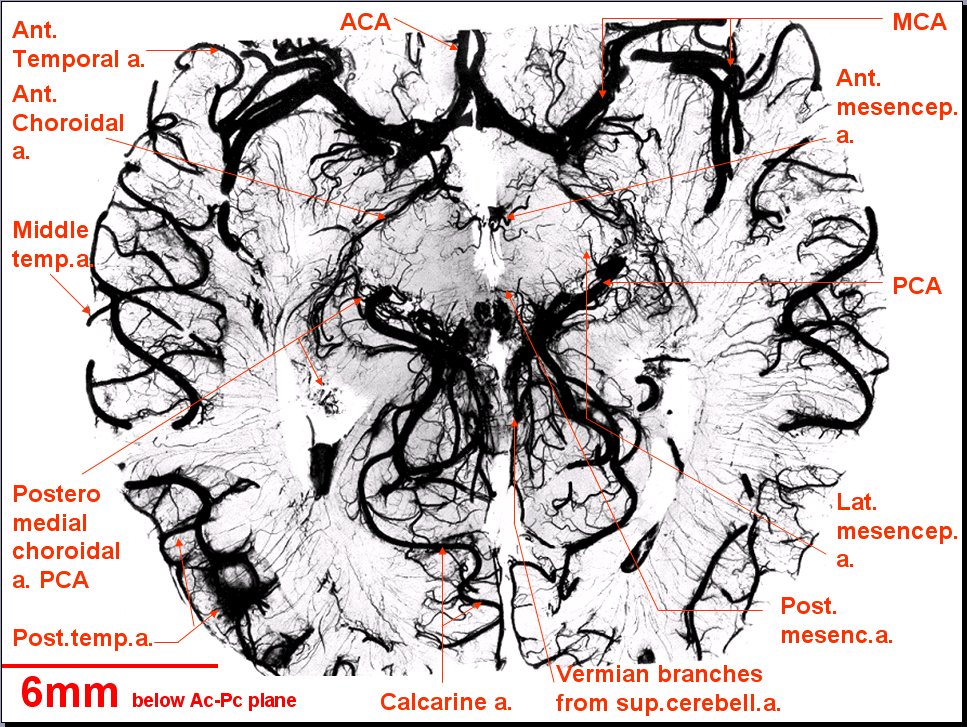

Neurovasculature: Atlas of Brain Arteries in Horizontal Section

Atlas of Brain Arteries (Horizontal Section): OverviewAtlas

Looking At: Neurovasculature > Atlas of Brain Arteries (Horizontal Section) > Atlas > Slide 22